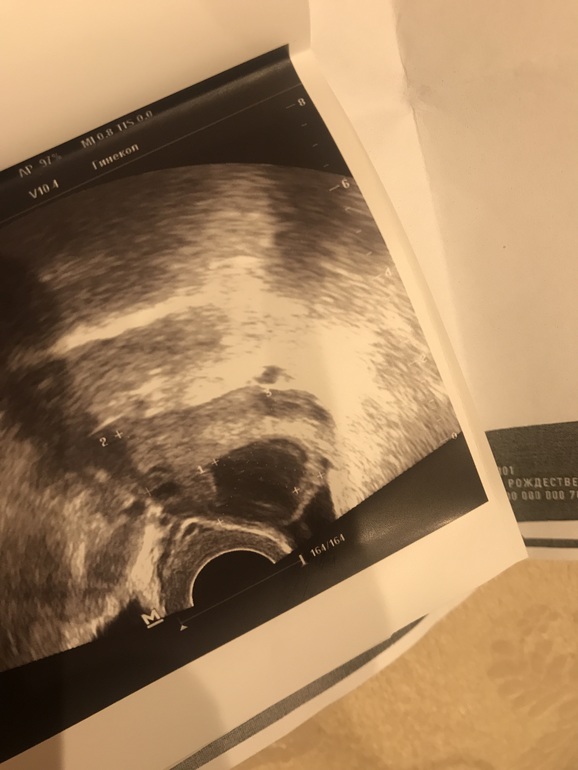

Месячный 1.04. С 9 дня делаю тесты, на 13 дц прям жирная, 15 день еще есть, но слабен, на 16 день совсем слабая. Параллельно график БТ веду: 15 дц 36,55, 16 дц 36,65, сегодня 17 дц 36,85! Ну все ж показывает, что где то на 15 дц была овуля!!! Иду вчера на узи! А она мне выдает: в правом яичнике доминантный фоликул 18,9 мм!!! Я чуть не встала и не упала! Как??? Дома начала изучать и вот что по фото ЖТ поняла, что не ошиблась ли наша специалист??? Посмотрите своим опытным взглядом на мое узи. ЖТили она права и это ДФ?

Если это ЖТ, то эндометрий она намерила 8,2, как считаете нормальный?